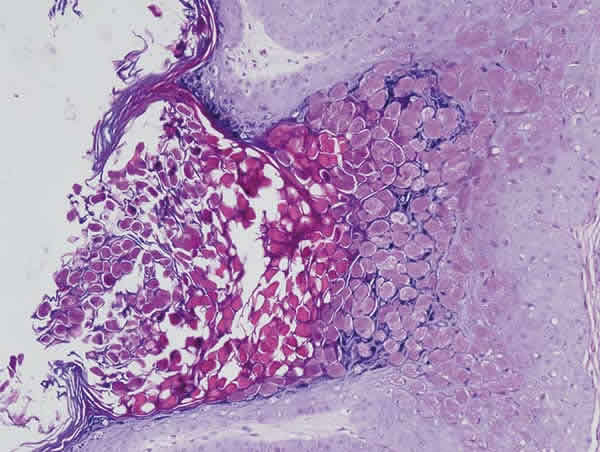

Mujer de 29 años que acude por un cuadro de enrojecimiento y picor en su ojo derecho (OD) de meses de evolución que no cede con colirios pautados en atención primaria. En la exploración destacamos hiperemia mixta con queratoconjuntivitis y reacción folicular intensa en conjuntiva tarsal inferior. Pápula redonda de 4 mm en borde libre de párpado superior OD compatible con molluscum contagiosum (fig. 1). Se decide pautar corticoides sin conservantes y lágrimas artificiales hasta la extirpación. Se realiza resección con cauterización de la base y se remite a anatomía patológica para su estudio histológico. El examen microscópico demuestra un patrón lobular con hiperplasia escamosa intradérmica. Estos lóbulos maduran y emigran hacia superficie para desintegrarse. En el citoplasma de los queratinocitos aparecen inclusiones eosinófilas (cuerpos del mollusco) que junto con queratina serán expulsadas hacia el cráter central de la lesión (figs. 2, 3, 4 y 5). Tras 6 meses de seguimiento sin tratamiento permanece asintomático y no se han observado recurrencias.

Figs. 4 y 5. Cuerpos del molluscum, inclusiones eosinófilas ocupando la mayor parte del citoplasma de las células escamosas infectadas (x100 y x400).